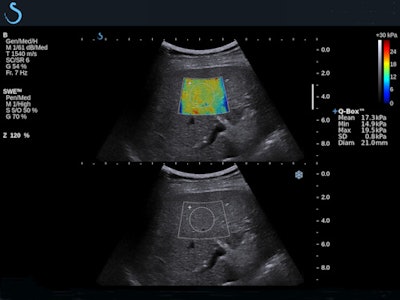

Evaluating liver stiffness

Over the past decade, several studies have demonstrated the benefits of SWE for assessing liver stiffness quantitatively, noninvasively, and accurately.7 SWE has been shown to yield accurate diagnostic measurement of liver fibrosis in a range of patients, from hepatitis C patients to cirrhosis, including those with ascites.8

One of the more recent studies found the moving images obtained this way accurately measured incidentally discovered liver lesions in patients with no history of liver disease; another found that SWE aided the detection of portal hypertension, a dangerous complication of cirrhosis.9 Two-dimensional images obtained noninvasively were especially important for monitoring the progression of liver disease in vulnerable patient populations such as those suffering from chronic viral hepatitis.